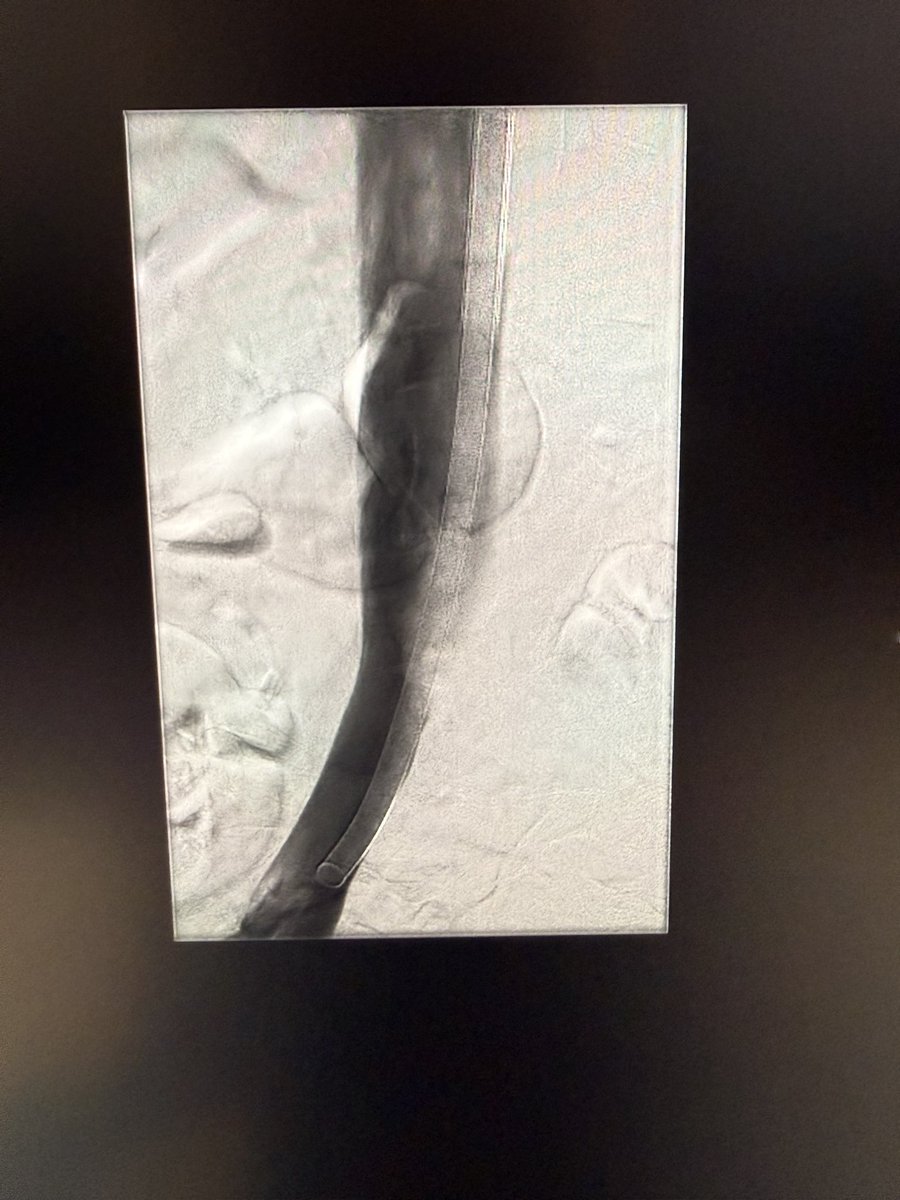

It was one of those days, #chogazi back at it again. Haven’t been posting many cases coz X has been atrocious recently, but we did perc esophageal varix embo with mesocaval shunt on this one - should I post more? @beckcj